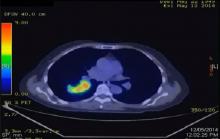

This video shows a completion pneumonectomy performed totally by video-assisted thoracoscopic surgery (VATS) on a 64-year-old female non-smoker. The patient underwent a right middle and lower lobectomy by thoracotomy in May 2014 for a T2N0M0 adenocarcinoma of the right lower lobe. The post-operative stay was prolonged for 10 days due to empyema. Repeat PET/CT scan in October 2014 showed a local recurrence in the upper lobe at the previous staple line. The patient was referred to the author’s institution for a second opinion. Her lung function was adequate and there were no other evidence of metastatic disease. She underwent a right VATS completion pneumonectomy.